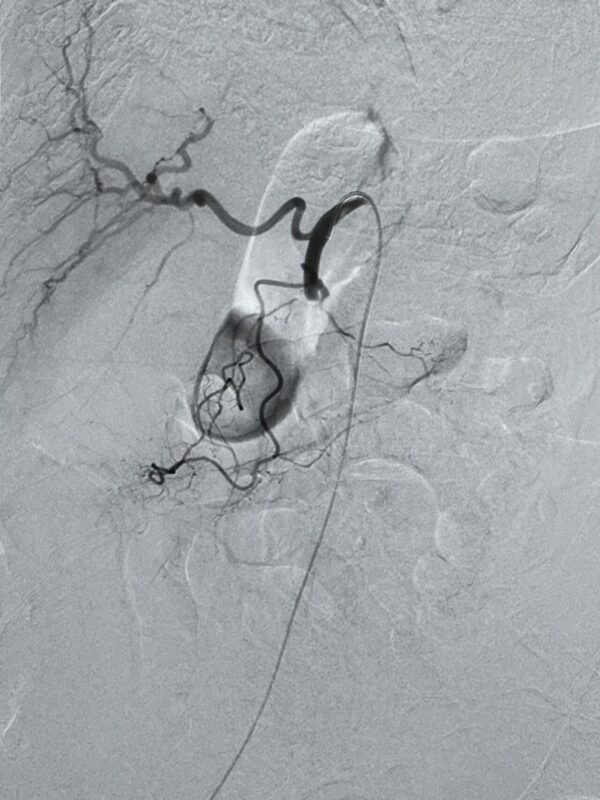

”Revascularization of the superior mesenteric artery (SMA) in a patient with acute mesenteric ischemia.

Selective catheterization of the SMA was performed, and 200.000 Ui bolus of urokinase were infused into the thrombus.

Subsequently, thromboaspiration of the occluded segment was carried out using a CAT-8 catheter (Penumbra).

After achieving recanalization, an additional 200,000 Ui bolus of urokinase was administered.

The final angiographic control demonstrated complete recanalization of the previously occluded artery, with opacification of all colic and jejunal vascular branches.

The patient then continued with an infusion of urokinase at a rate of 120,000 IU per hour.

Pre and post-treatment DSA are shown.